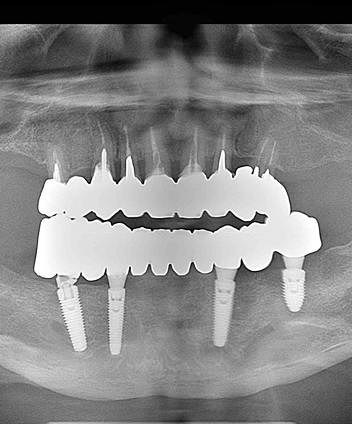

All-on-4(オールオンフォー)は、上顎・下顎に4本ずつのインプラントを埋入し、

その上に全ての人工歯を固定する画期的な治療法です。

従来のように10本以上のインプラントを必要とせず、

骨のある部分を活かして傾斜埋入することで、骨移植なしでも対応できるケースが多いのが特徴です。

手術当日に仮歯を装着できる「即時荷重」に対応しており、

「手術をしたその日から食事や会話ができる」という大きなメリットがあります。